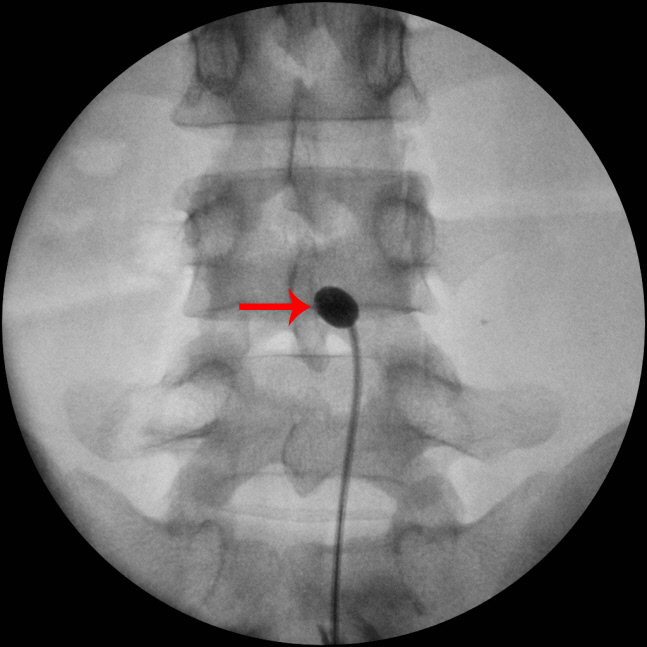

환자처럼 고령이어서 수술이 부담스러운 경우라면 신경성형술을 우선적으로 고려해볼 수 있다. 신경성형술은 국소 마취한 후 특수한 카테터를 삽입해 유착된 부분을 제거하고 약물을 주입해 염증을 치료하는 시술이다. 최근에는 카테터 끝에 풍선을 달아서 유착부위와 척수 신경이 빠져나가는 구멍인 신경공의 좁아진 부위를 확장하고, 약물을 주입하는 풍선확장 신경성형술이 시행되고 있다.

환자는 풍선확장 신경성형술을 받았다. 다행히 시술은 성공적으로 끝났다. 시술 후 환자는 허리와 엉덩이 통증이 많이 가벼워졌다며 만족했다. 환자의 경우에서도 알 수 있듯이 고령의 환자에게 신경성형술은 안전하면서도 효과가 좋은 시술이다.